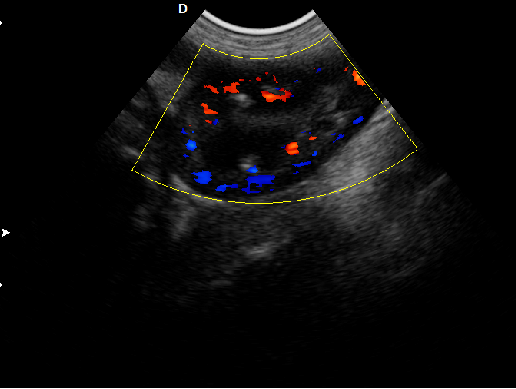

P5-VET獸用彩超機脊椎檢查圖

脊椎檢查:

脊柱裂的預防和確診,一般在動物懷孕以后定期給動物做超聲檢查,通過超聲、超聲檢查可以早期發現動物胎兒是否合并了脊柱裂或是神經管閉合不全。